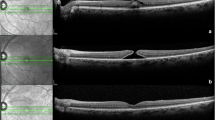

A detailed survey of consecutive optical coherence tomography (OCT) scans was done in a high-throughput ocular imaging service to ascertain cases of vitreomacular adhesion (VMA) and VMT using a departmental classification system. Analysis was done on the stages of traction, visual acuity, and association with other macular conditions.

In total, 4384 OCT scan episodes of 2223 patients were performed. Two hundred and fourteen eyes had VMA/VMT, with 112 eyes having coexisting macular pathology. Of 102 patients without coexisting pathology, 57 patients had VMT grade between 2 and 8, with a negative correlation between VMT grade and number of Snellen lines (r=−0.61717). There was a distinct cutoff in visual function when VMT grade was higher than 4 with the presence of cysts and sub retinal separation and breaks in the retinal layers.

VMT is a common encounter often associated with other coexisting macular pathology. We estimated an incidence rate of 0.01% of VMT cases with reduced vision and without coexisting macular pathology that may potentially benefit from intervention. Grading of VMT to select eyes with cyst formation as well as hole formation may be useful for targeting patients who are at higher risk of visual loss from VMT.